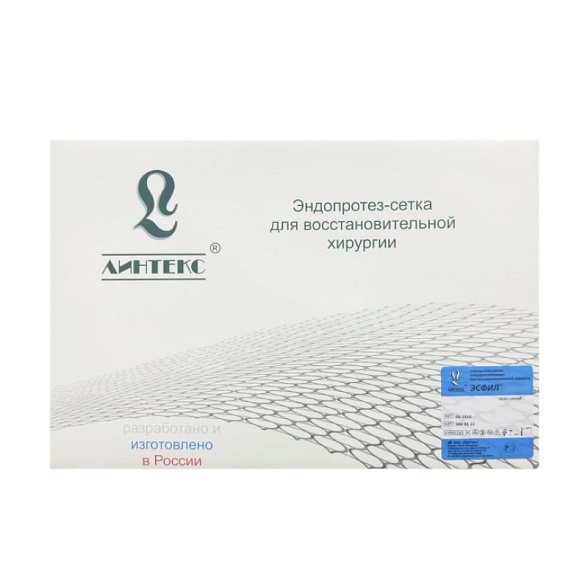

Эндопротез-сетка (сетка хирургическая) полипропиленовый для восстановительной хирургии ЭСФИЛ лёгкий, 20х10 см, Линтекс

Эндопротез-сетка полипропиленовая ЭСФИЛ лёгкий для восстановительной хирургии

Эндопротез-сетка ЭСФИЛ лёгкий от компании «Линтекс» — это современное и надежное решение для пластики грыж и восстановления мягких тканей в абдоминальной хирургии. Изделие изготовлено из высококачественного монофиламентного полипропилена, что обеспечивает оптимальное сочетание прочности, биологической инертности и удобства для хирурга.

| Торговая марка / Бренд | ЭСФИЛ (ESFIL), Линтекс (Lintex) |

| Страна производства | Россия |

| Упаковка | Индивидуальная двойная упаковка (блистер + внешний пакет) |